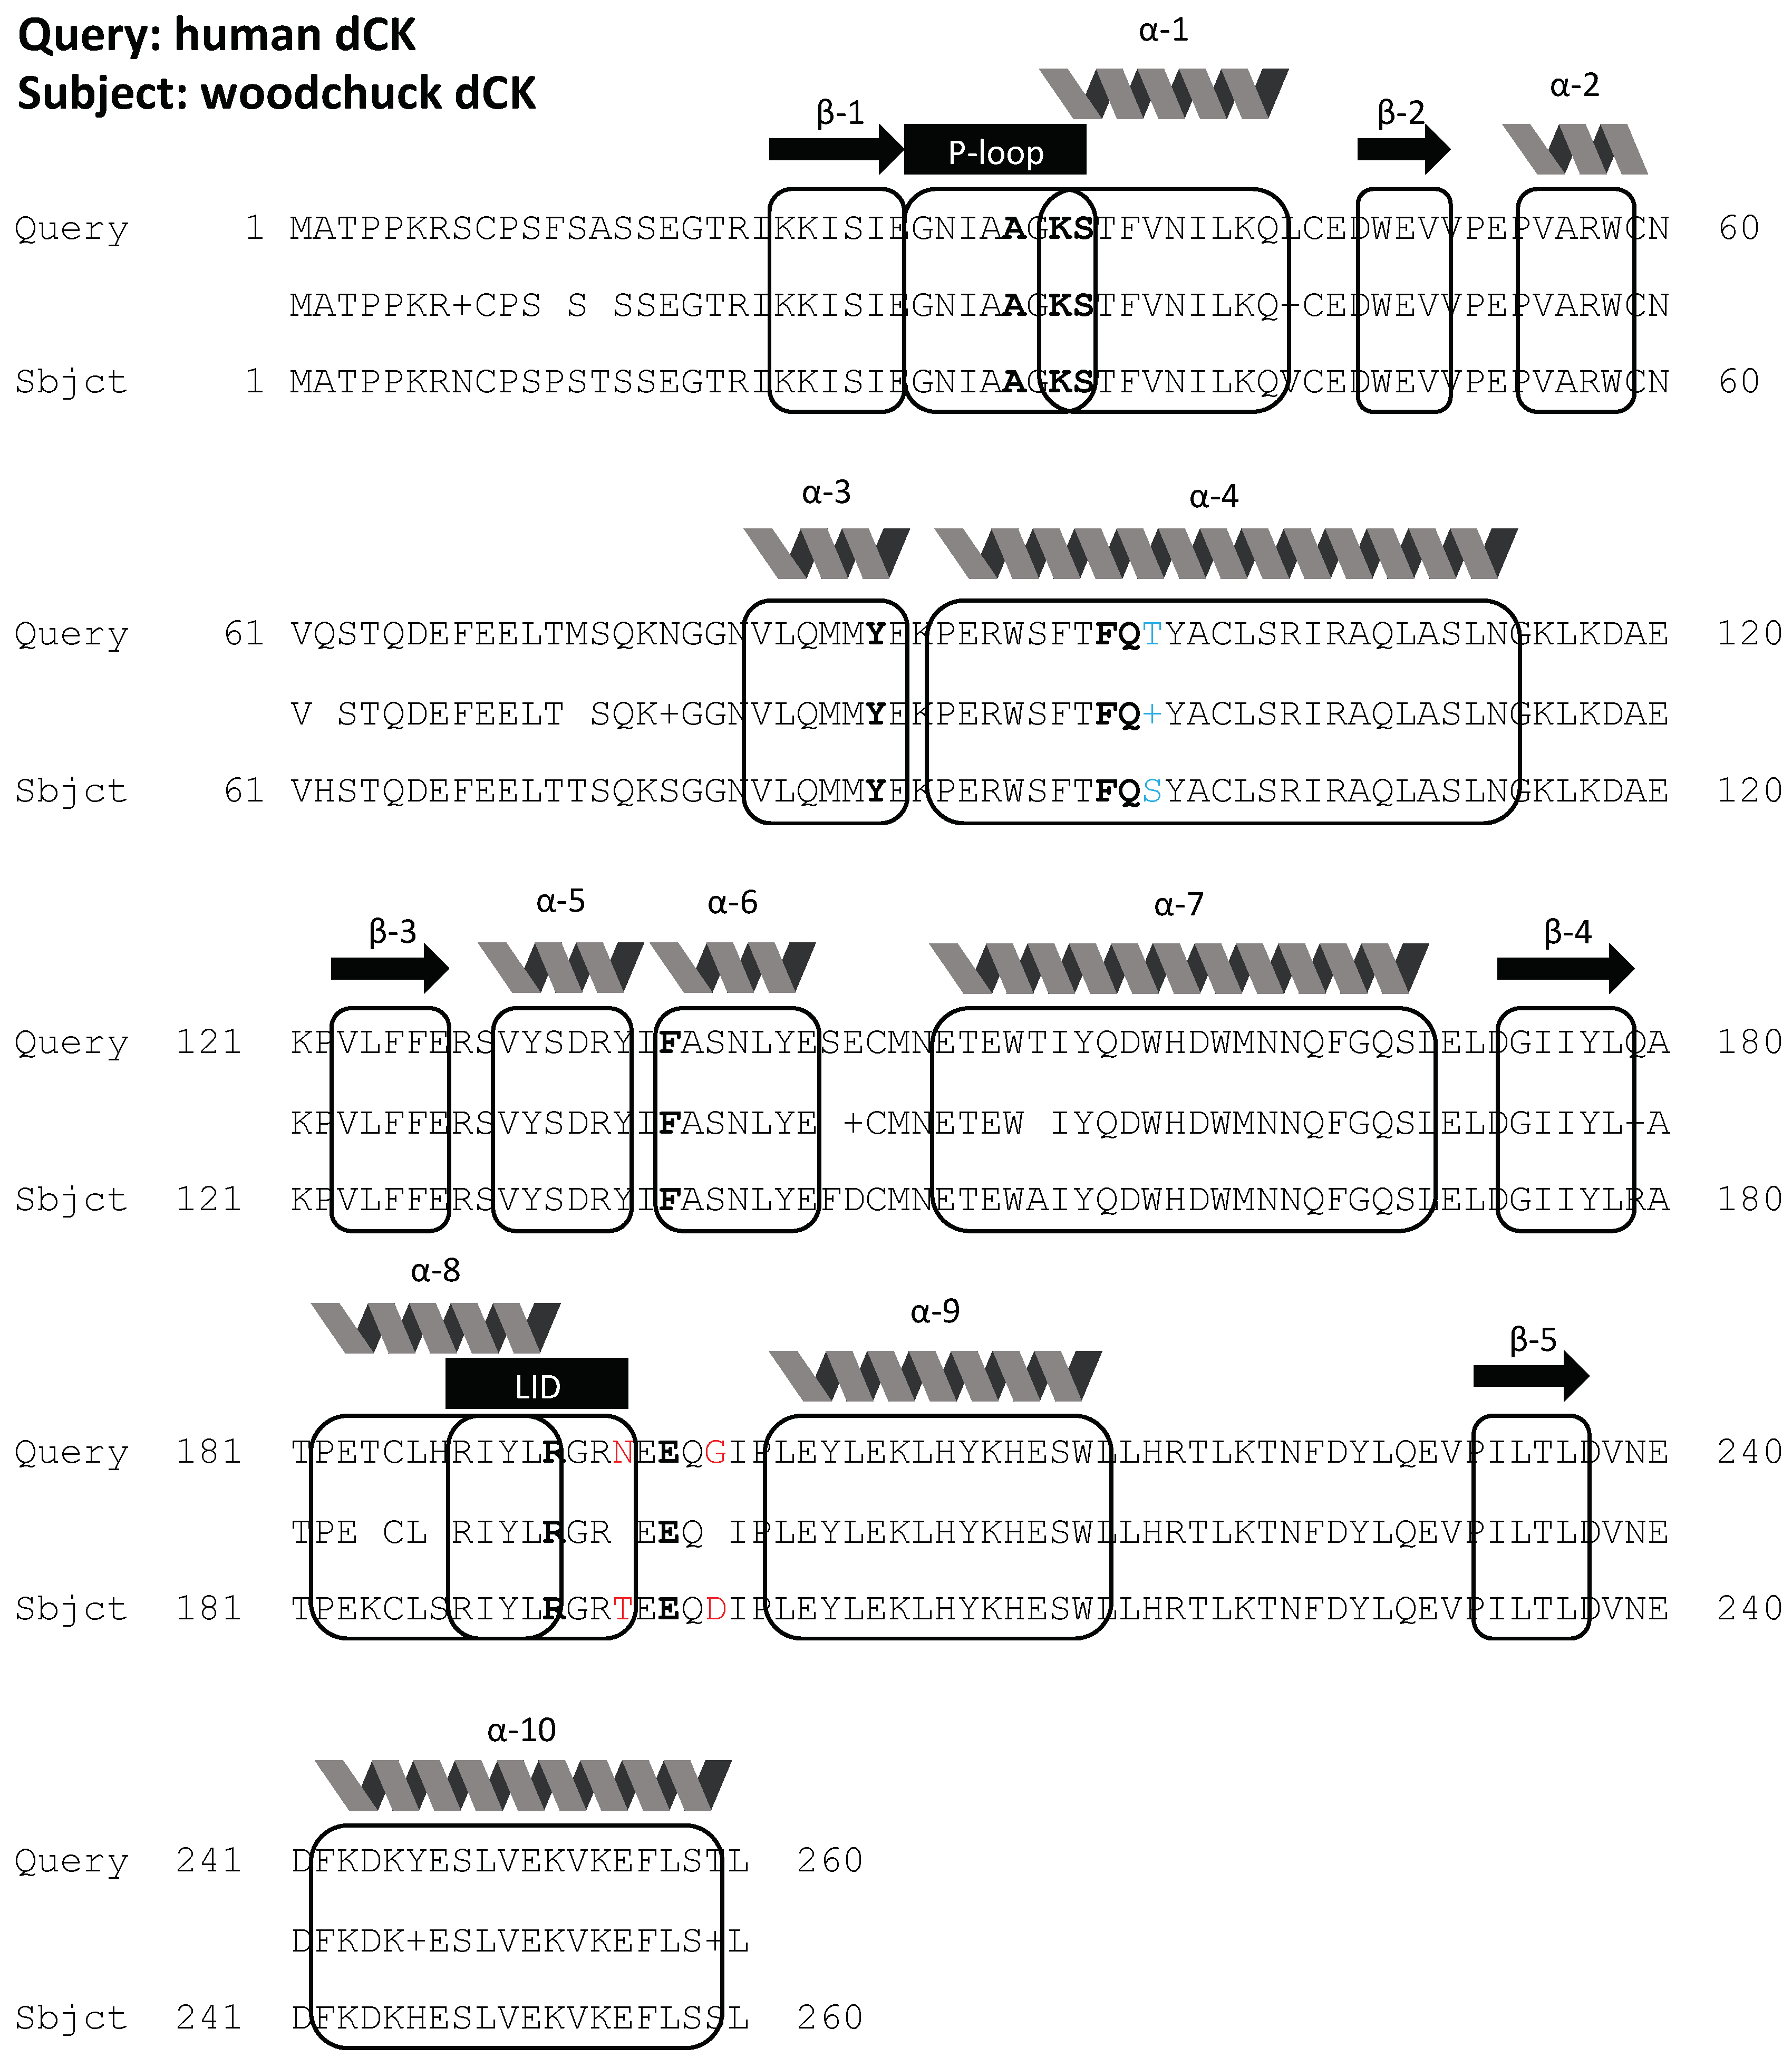

2.1. Bioinformatics

4.2. Bioinformatics

4.2.2. Woodchuck Data